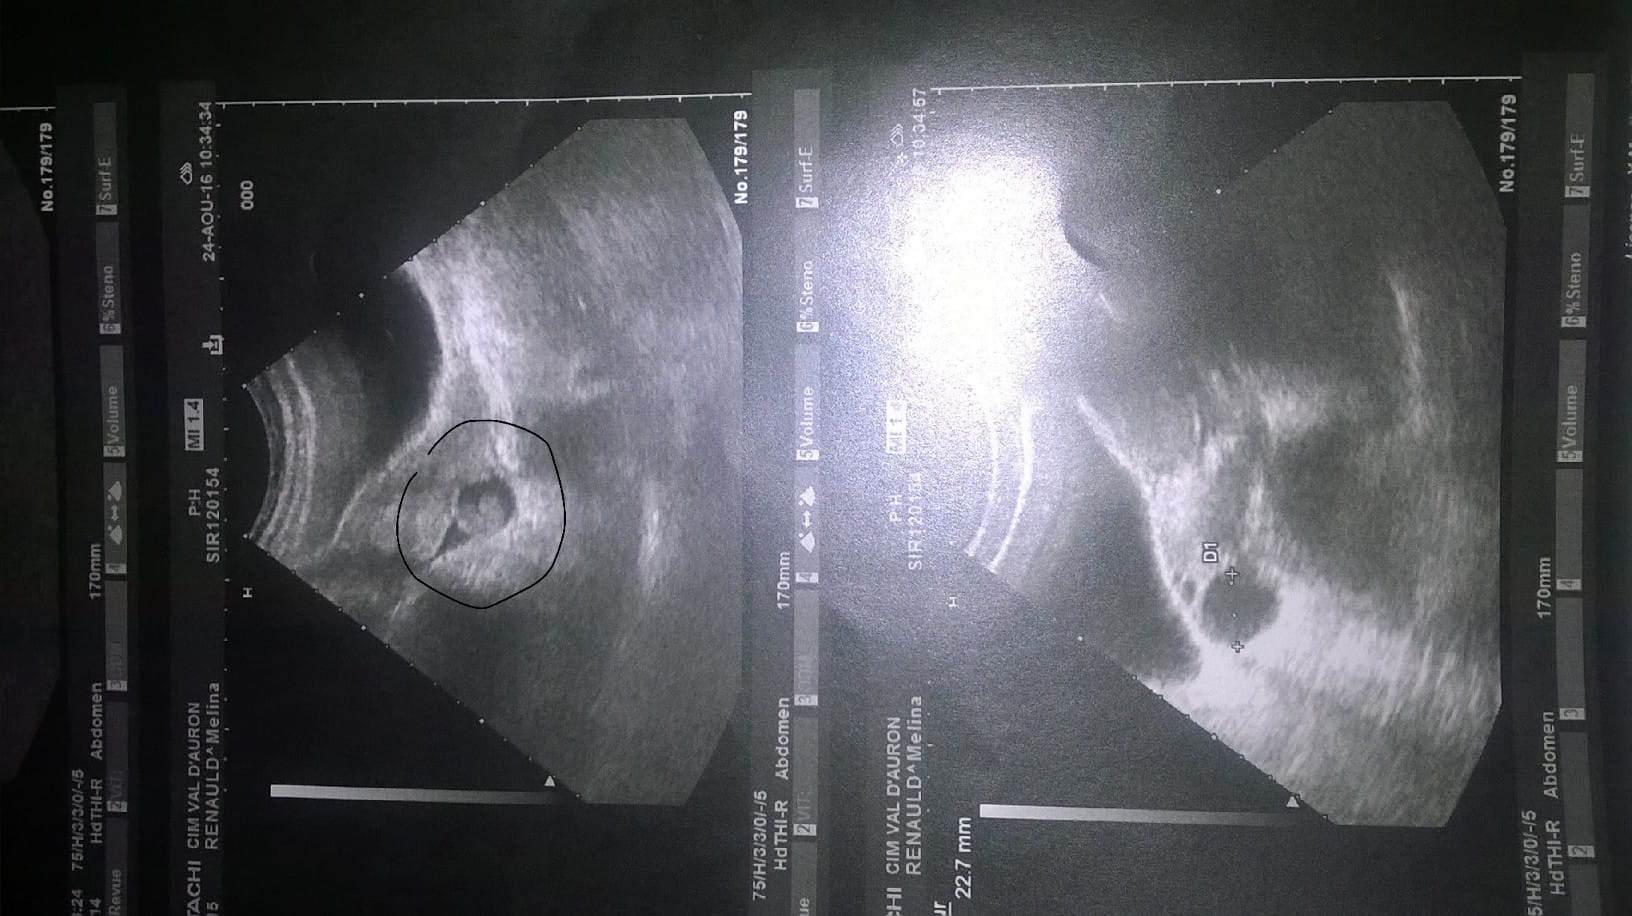

Je vous met la photo de mon échographie :

Je vais essayer de faire court ! Voilà depuis juillet que mon soucis dure. Tous le mois de juillet j'ai eu des symptômes de grossesse : du moins ce que mon médecin m'a dit (nausées, fatigue, bouffée de chaleur, vertiges, seins tendus, envie fréquente d'uriner...) mais celui qui dure depuis sont les douleurs aux ovaires (depuis les autres symptômes sont partis sauf vertiges et ovaires). Test de grossesse Négatif, donc mon médecin en a conclut à une infection urinaire mais malgré les médocs les douleurs aux ovaires persistent. J'ai eu mes rrrrr le 27 juillet mais pas comme d'habitude (4 jours seulement, sans douleurs, pas abondants et sur la fin couleur un peu rosé). Donc j'ai du aller faire une échographie abdominal, il m'a dit qu'il y avait une anomalie avec du liquide derrière l'ovaire donc il m'a envoyé aux urgences pour examens complémentaire. J'ai eu une échographie vaginal, et donc elle m'a dit qu'il n'y avait aucun soucis (utérus vide, ovaires tout à fait normal). Donc deux échographie et deux avis différents. Tous mon demandé (médecins, gynéco) si j'avais fais prise de sang Bêta HCG (deux et négatif).